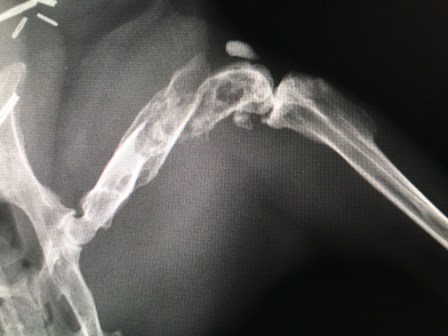

It’s been 4 weeks since Aeryn broke her leg again, this time in 2 places at the right femur (see attached X-ray).  Up until very recently, she and her cagemate Tegan have been confined to their part of the bunny condo to limit her movements so she can heal.  Aeryn has been acting in a completely normal fashion, and even started hopping back into their litterbox about a week ago.

Given that, we have decided to let them come out of their cage as before.  She is hopping and getting about normally.  Her leg may not have healed completely as much as it ever will, but it is clearly holding up, and it’s impossible to immobilize her completely at any rate.  And if you look closely at her when she is sitting, you can tell that her right leg’s angle is just a tiny bit off from the left one.  Given how the leg broke, a fully restored heal was impossible.  And of course they don’t race around anywhere as much as they used given that Aeryn just turned 10 and Tegan is 9.  But if we didn’t have the X-ray, we would be convinced that she was faking the whole thing!